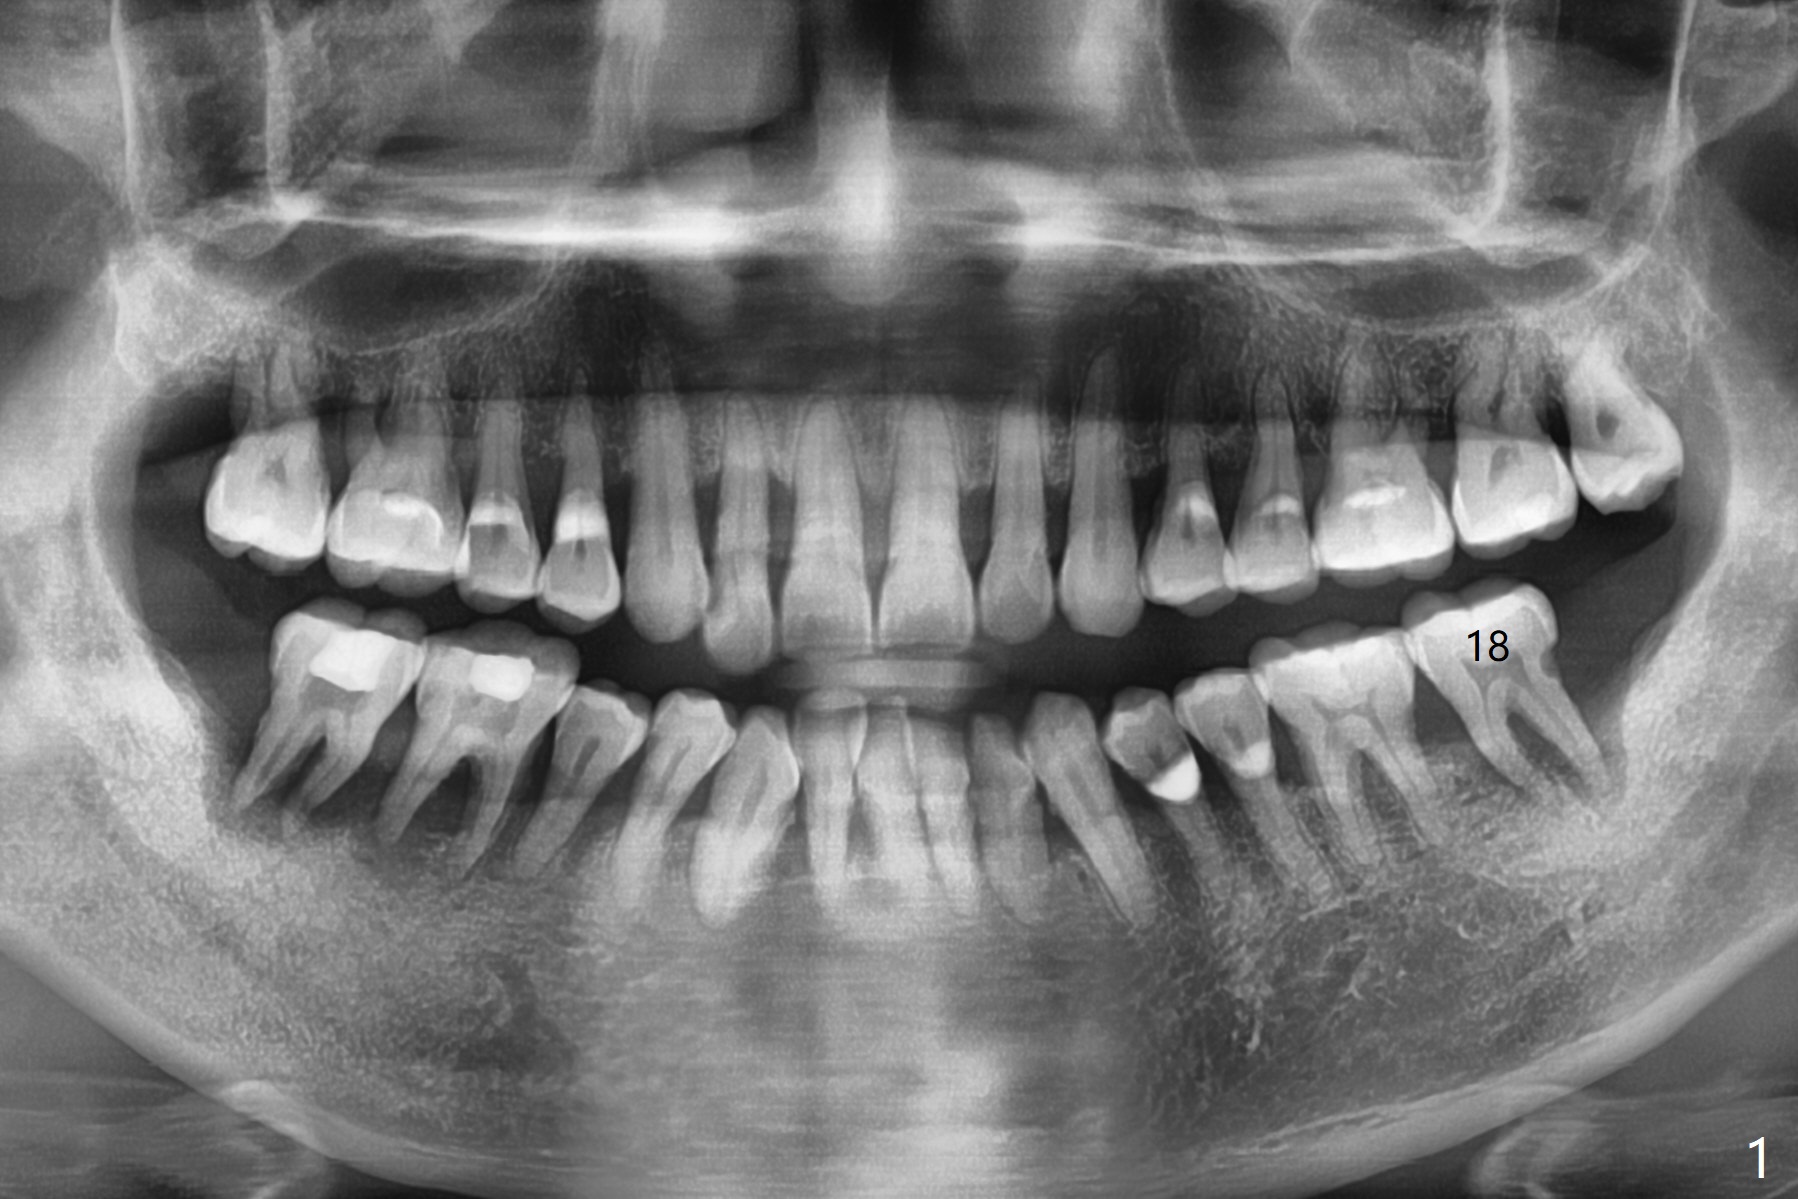

A 55-year-old man presents to clinic with nocturnal pain associated with the tooth #18 (Fig.1). After extraction and removal of granulation tissue, mineralized cortical allograft (particle size: 125μm – 850μm)) hydrated with .5 ml of .3 mg/ml of rhPDGF-BB (one component of GEM21S) is placed in the sockets with a thin septum (Fig.2 *). Periodontal glue is applied to the top layer of the bone graft (Fig.3 blue curved line). It appears that the bone graft becomes less mobile. GEM Cap RCM (regenerative collagen membrane, 9-12 month resorption time) is placed with the glue applied to the periphery of the cap, which seems to be quite stable (Fig.4). No suture is needed.